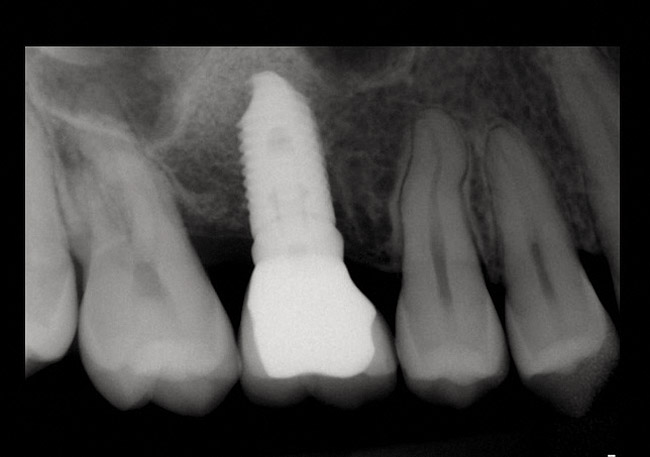

Fig 14. Peri-apical X-ray of the site immediately following sinus floor elevation and implant insertion.

Figure 14

Fig 15. Peri-apical X-ray 5 months following the procedure. Notice bone mantel over the implants.

Figure 15